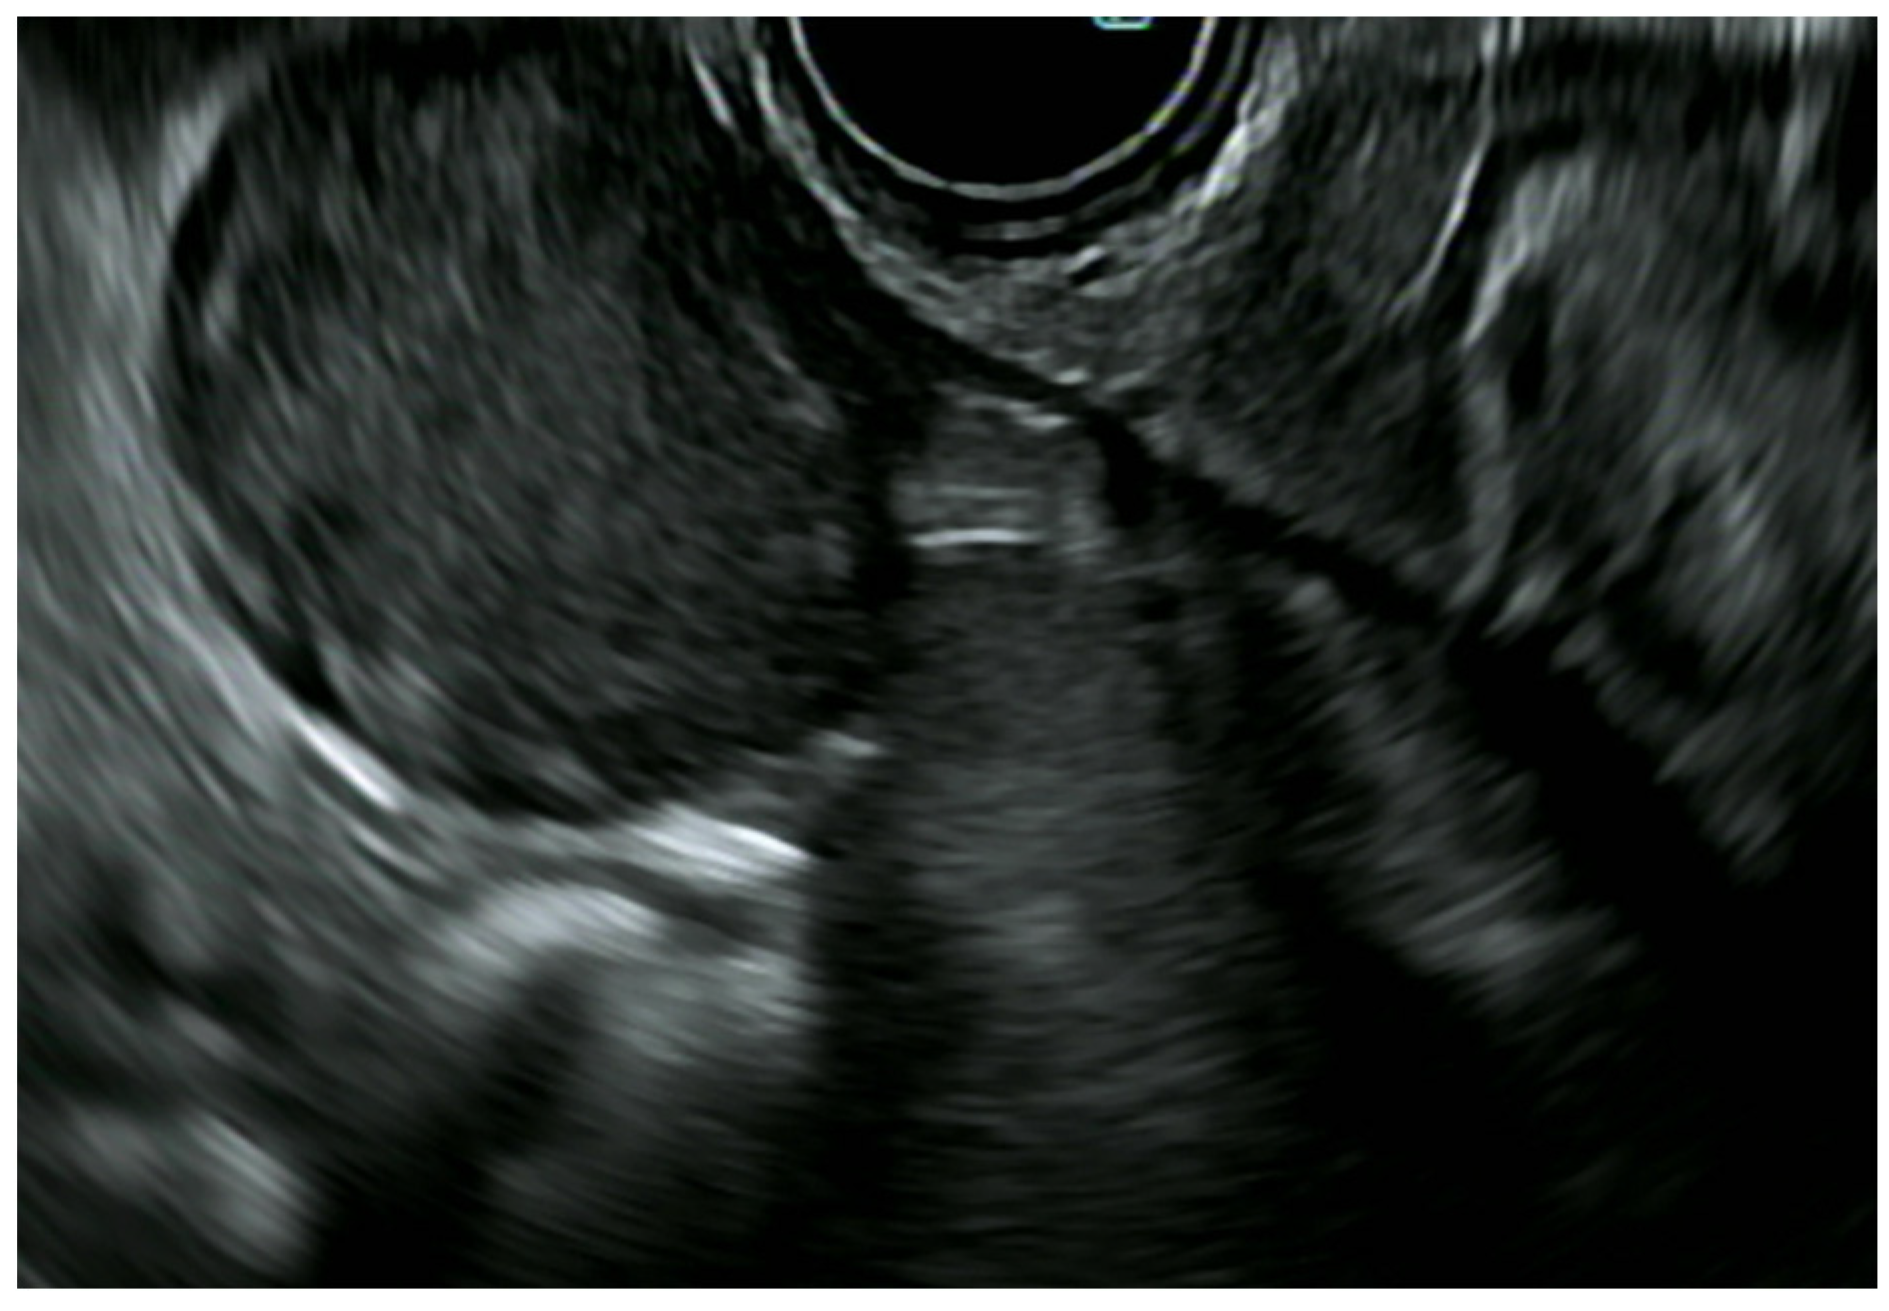

5.1.1. Esophageal Cancer

5.1.3. EUS in Advanced Esophageal Cancer

5.2. Esophageal Subepithelial Lesions